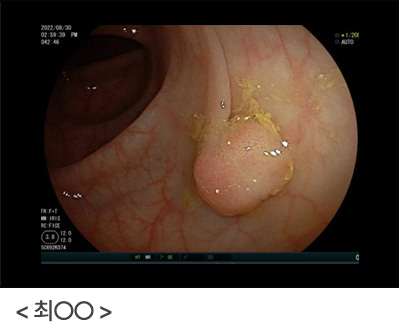

위암도 초기에는 대부분 아무런 증상이 없는 경우가 많으며, 정기적인 위내시경 도중 우연히 발견되는 경우가 많고, 진행된 위암의 경우, 오심, 구토, 소화불량 등의 증상이 나타날 수 있습니다. 정기적인 위내시경 검사를 통해 위를 직접 관찰하고 필요시 조직 검사를 통해 위암이 의심되는 부위를 확인함으로써 위암을 조기에 발견할 수 있습니다.

단 한 번의 내시경 검사로, 위암을 진단 못할 수도 있습니다. 위통이나 속 쓰림, 소화불량 등의 증상이 있고 위암일 가능성이 조금이라도 있다면 다시 위내시경을 시행하여 확인하는 것이 중요합니다. 위내시경 시행 후 괜찮다고 안심하지 마시고, 증상이 지속되거나, 위암의 고위험군이라면 지속적인 위내시경 검사를 하시는 것이 좋습니다.